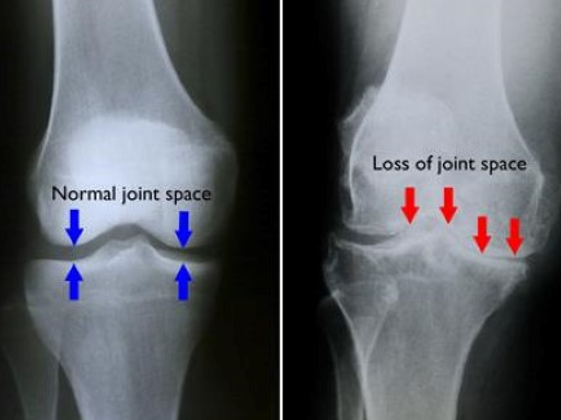

19

Q

Degenerative Joint Disease/Arthritis Imaging

• XR:

• Recommended views

• Weight-______ views of affected joint

• Optional views

• S______ view

• _ _ view in 30 degrees of flexion

• Look for:

• Joint _____ narrowing

• Osteo_____

• Subchondral s______

• Subchondral c_____

• MRI: ______ the urge, especially in advanced disease

• Weight-bearing views of affected joint

• Sunrise view

• PA view in 30 degrees of flexion

• Joint space narrowing

• Osteophytes

• Subchondral sclerosis

• Subchondral cysts

• MRI: Resist the urge, especially in advanced disease